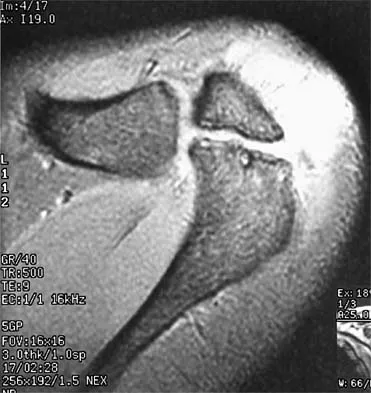

Figure 22 shows the MRI scan of a 20-year-old female basketball player who has pain over the anterior knee that interferes with her performance. Examination reveals phase III Blazina patellar tendinosis. Management should consist of

Explanation